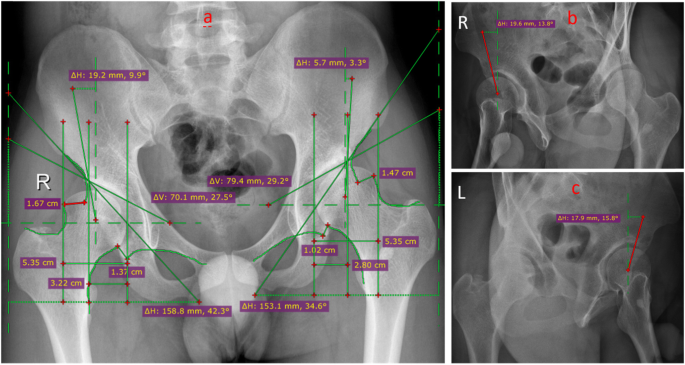

The radiographic evaluations were performed with a standard anteroposterior pelvis projection and a false profile view (Fig. 2). The degree of preoperatively hip dysplasia and the reorientation of the achieved acetabulum were assessed by measuring the anterior center-edge angle, the lateral center-edge angle, the total femoral coverage, the sharp angle, the acetabular sign, Shenton’s line intact, Calve’s line intact, and the acetabular index angle (Fig. 3a–c and Fig. 4a–c). The presence and grade of osteoarthrosis was graded according to the criteria of Tönnis (1987). Meanwhile, clinical examinations including the impingement test, the apprehension test, the Trendelenburg sign, and the range of movement (ROM) were used to evaluate the hip function.

According to clinical data, all the DDH indexes were similar between the groups in pre-operation and post-operation except a sharp angle in pre-operation (p = 0.007). Compared with pre-operation, the total femoral coverage, the anterior center-edge angle, the lateral the center-edge angle, the sharp angle, and the acetabular index were remarkably improved to the normal value of the hip. Meanwhile, Shenton’s line intact and Calve’s line intact were consecutive and smooth lines in post-operation and in all cases. In both groups modified S-P and group I-I, the positive incidence of the crossover sign in post-operation was significantly lower than the one in pre-operation (all of p values were 0.000), and there was no significant difference between the groups (pre-operation: p = 0.600; post-operation: p = 0.463) Tables 4 and 5.